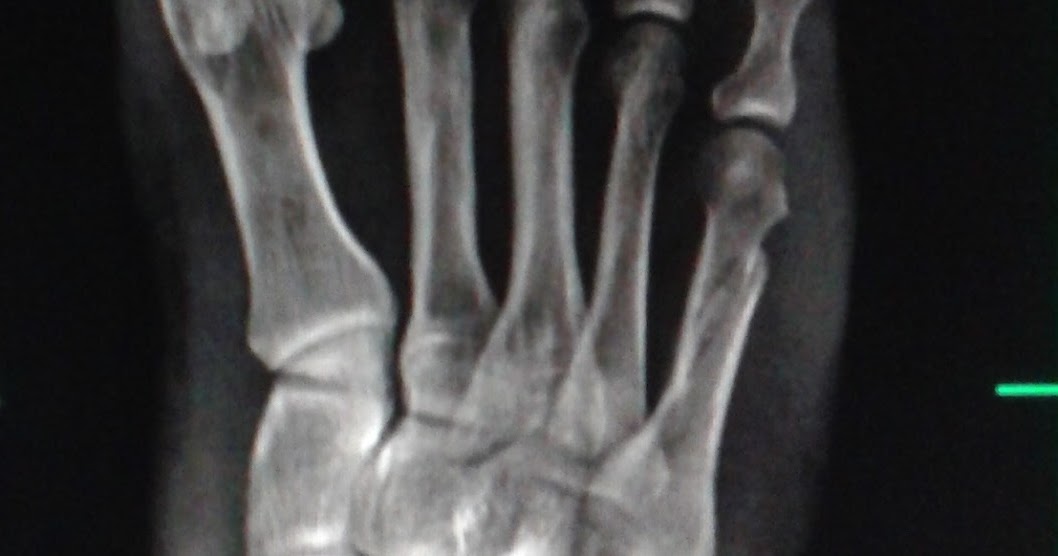

5th Metatarsal Base Fractures are among the most common fractures of the foot and are predisposed to poor healing due to the limited blood supply to the specific areas of the 5th metatarsal base. Diagnosis is made with plain radiographs of the foot. Treatment can include protected weight bearing, immobilization or surgery depending on location.. As fraturas dos metatarsos são comuns e podem ocorrer na base, no terço médio, no colo ou na cabeça do osso. O que vai determinar o nível de gravidade da fratura são fatores como o local, extensão e se houve desvio ou não. Causas. As fraturas dos metatarsos podem ter variados fatores causadores. Elas podem ocorrer por causa de uma.

Fifth metatarsal Fractures